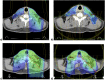

Methods: 10 patients treated definitively with radiation for oropharyngeal, oral cavity or nasopharyngeal carcinoma were compared. Only patients ideally suited for SF-IMRT plans were included. The glottic larynx, supraglottic larynx, arytenoids, pharyngeal constrictors, oesophagus, brachial plexus and target volume coverage in the LAN were compared between WF-VMAT and SF-IMRT.

Results: Volumetric-modulated arc therapy (VMAT) yielded statistically significant decreases in maximum dose to the arytenoids and mean dose to the oesophagus. There was no difference in dose to the glottic larynx, supraglottic larynx, pharyngeal constrictors and brachial plexus. WF-VMAT led to improved coverage to 50/2 Gy fraction equivalent in LAN compared with SF-IMRT using an anteroposterior (AP) LAN field but no difference to the 60/2 Gy fraction equivalent between SF-IMRT and WF-VMAT using AP/posterior-anterior LAN boost.

Conclusion: WF-VMAT affords equivalent glottic and supraglottic larynx dose and lower dose to the arytenoids and oesophagus. WF-VMAT better covers most LAN target structures. Given these findings as well as concerns with matchline cold spots or hotspots with SF-IMRT, patients requiring comprehensive elective nodal irradiation should typically be treated with WF-VMAT.